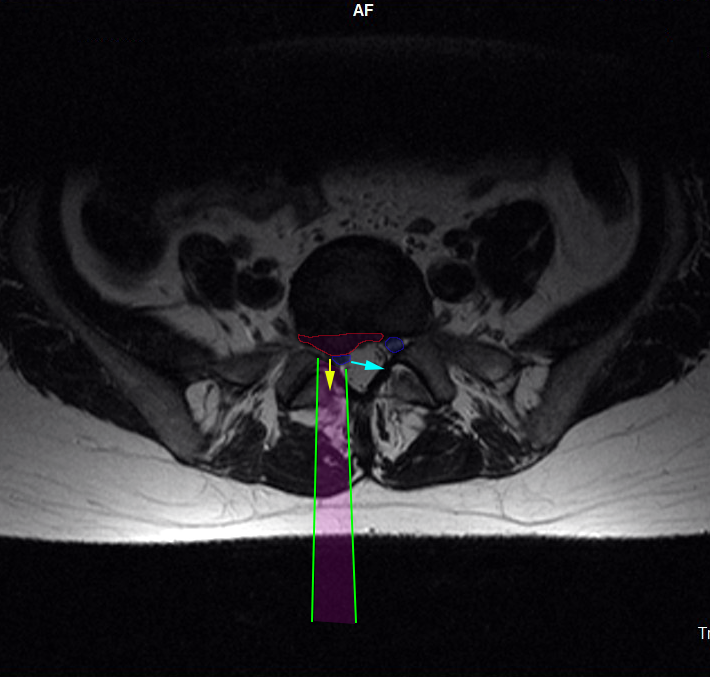

Η προσπέλαση (πράσινες γραμμές) της οσφυϊκής μικροχειρουργικής δισκεκτομής γίνεται με μικρή αποκόλληση των μυών της σπονδυλικής στήλης, διάνοιξη θυρίδας (οπής) στους συνδέσμους που καλύπτουν το νεύρο και σε ελάχιστο τμήμα του οσφυϊκού πετάλου. Το οσφυϊκό νεύρο (μπλέ) παρεκτοπίζεται και η κήλη (φούξια) αφαιρείται (κίτρινο βέλος). Όταν χρειάζεται, και από την ίδια προσπέλαση αφαιρείται και το περιεχόμενο του δίσκου, προκειμένου να επιτευχθεί πληρέστερη αποσυμπίεση του νεύρου. |